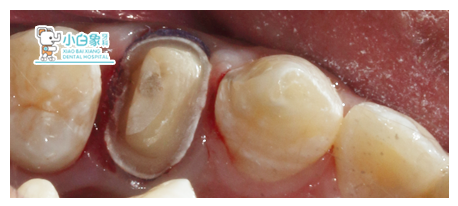

备牙

戴临时冠